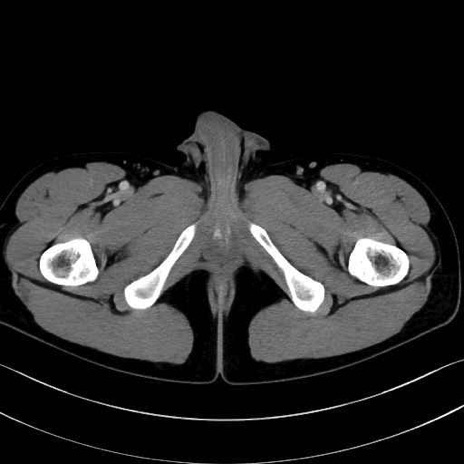

4. 深層外旋六筋(股関節の深部)

梨状筋 (Piriformis)

内閉鎖筋 (Obturator internus)

外閉鎖筋 (Obturator externus)

大腿方形筋 (Quadratus femoris)